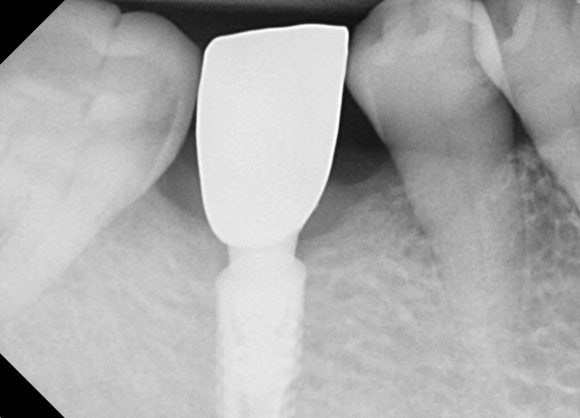

20250404

크라운을 붙인 날은 치료가 종료되는 날입니다.

엑스레이를 촬영해서 이물질이 남아있진 않은지 한 번 더 확인합니다.